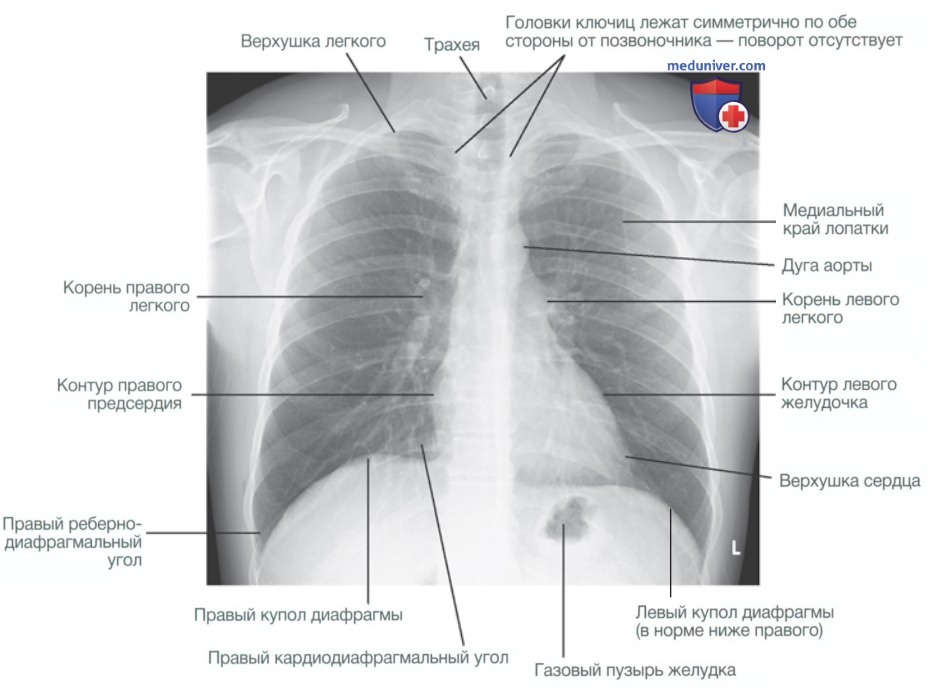

Что такое малоконтрастная рентгенограмма органов грудной клетки